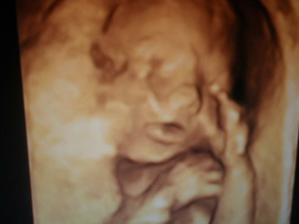

V maminčiným bříšku mi bylo už moc těsno,tak jsem se rozhodla přijít mezi vás a to 16.2.2010 v 11.20hod.Moje váha:3600g a 48cm......jsem síce prcek,ale já to doženu🙂Ve 2.měsícich jsem vážila 5160g a měřila 58cm.....Pořád jenom hajám,papám,čúram a kakám,ale hlavně opravdu moc dlouho a ráda spinkám.Vydržím celou noc,mamka se jen modlí,aby to takhle bylo pořád a ona si odpočinula🙂jsem tak hodnoučká,že ani neví že mně má🙂 2-4m:....už hodně vnímám,reaguju na hračky,poznávám lidi,ráda se koupu,krásně držím hlavičku,spinkám celou noc,mám už naušničky a za sebou první dovolenou mimo ČR.....pořád se směju,....Ve 3.měsícich jsem vážila 6470g a měřila 57cm.Maminka má málo mlíčka tak mě dokrmuje Nutrilonem,docela mi šmakuje......Ve čtyřech měsícich jsem vážila 7kg a měřila 63cm...